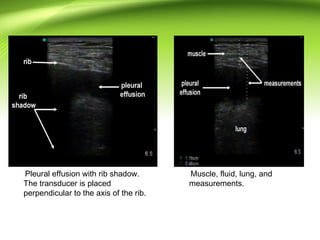

Pleural effusion with rib shadow.

The transducer is placed

perpendicular to the axis of the rib.

Muscle, fluid, lung, and

measurements.